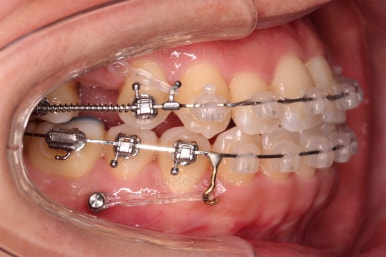

아랫니는 중앙선을 맞추기 위해서 미니스크류를 이용해 한 쪽으로 당기는 중이고요.

윗니 임플란트 할 자리는 적절히 계속 맞춰줍니다.

임플란트 할 공간도 여유롭게 마련이 되었네요.

임플란트는 뿌리 부분 식립 -> 3~6개월 기다림(뼈와 임플란트가 단단히 붙을 시간이 필요) -> 머리 부분을 완성하고 마무리

따라서 교정치료가 100% 끝나기 전에, 임플란트 공간만 마련되면 바로 식립을 하게 됩니다.

임플란트 뿌리 부분이 먼저 식립되었고요.

뼈와 잘 붙으라고 잇몸을 잘 꼬메어 줍니다.

최종 보철이 올라갈 3~6개월 기간동안 디테일한 조절을 더 해주고 교정과 임플란트를 동시에 마무리 합니다.